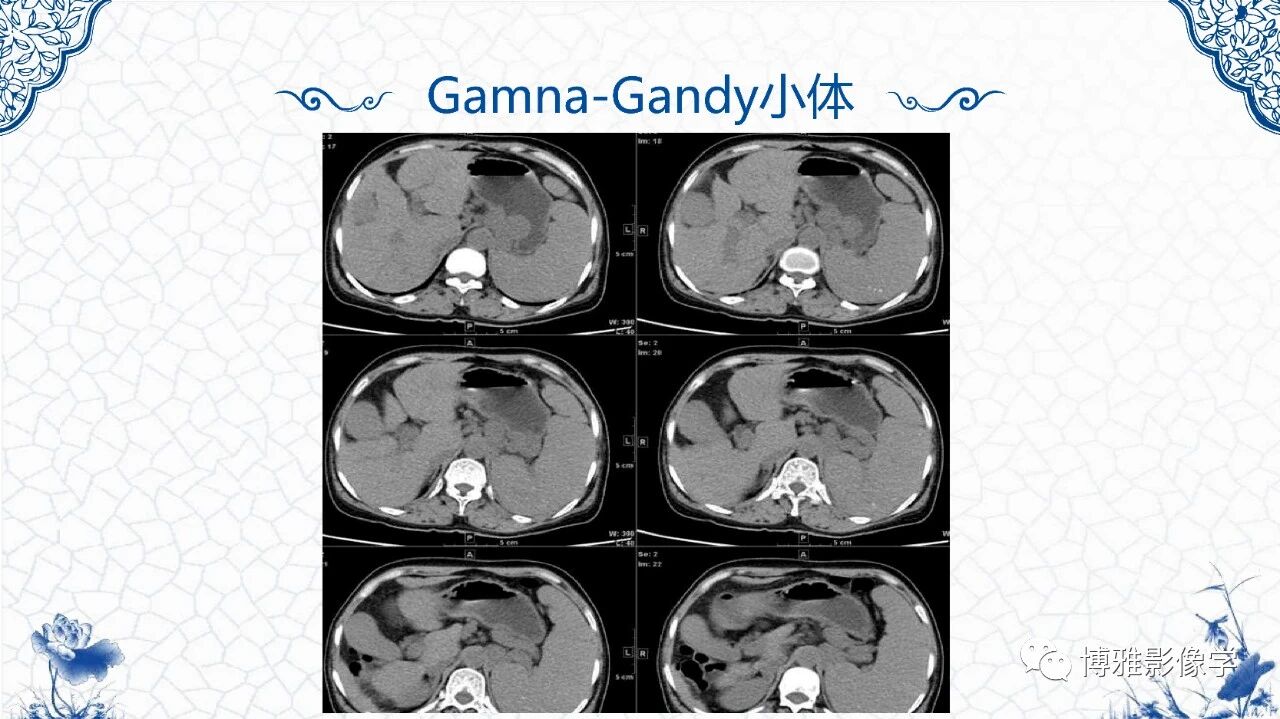

[腹盆] 脾脏非肿瘤影像诊断

脾脏非肿瘤影像诊断